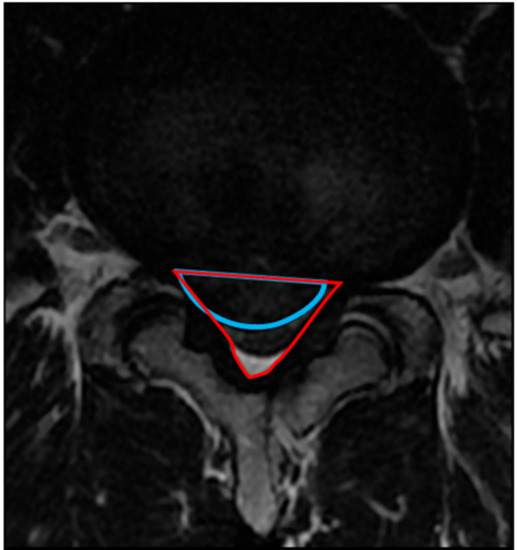

2.4.2. Occupancy Ratio of the Spinal Canal by the Protruded Nucleus Pulposus (NP)